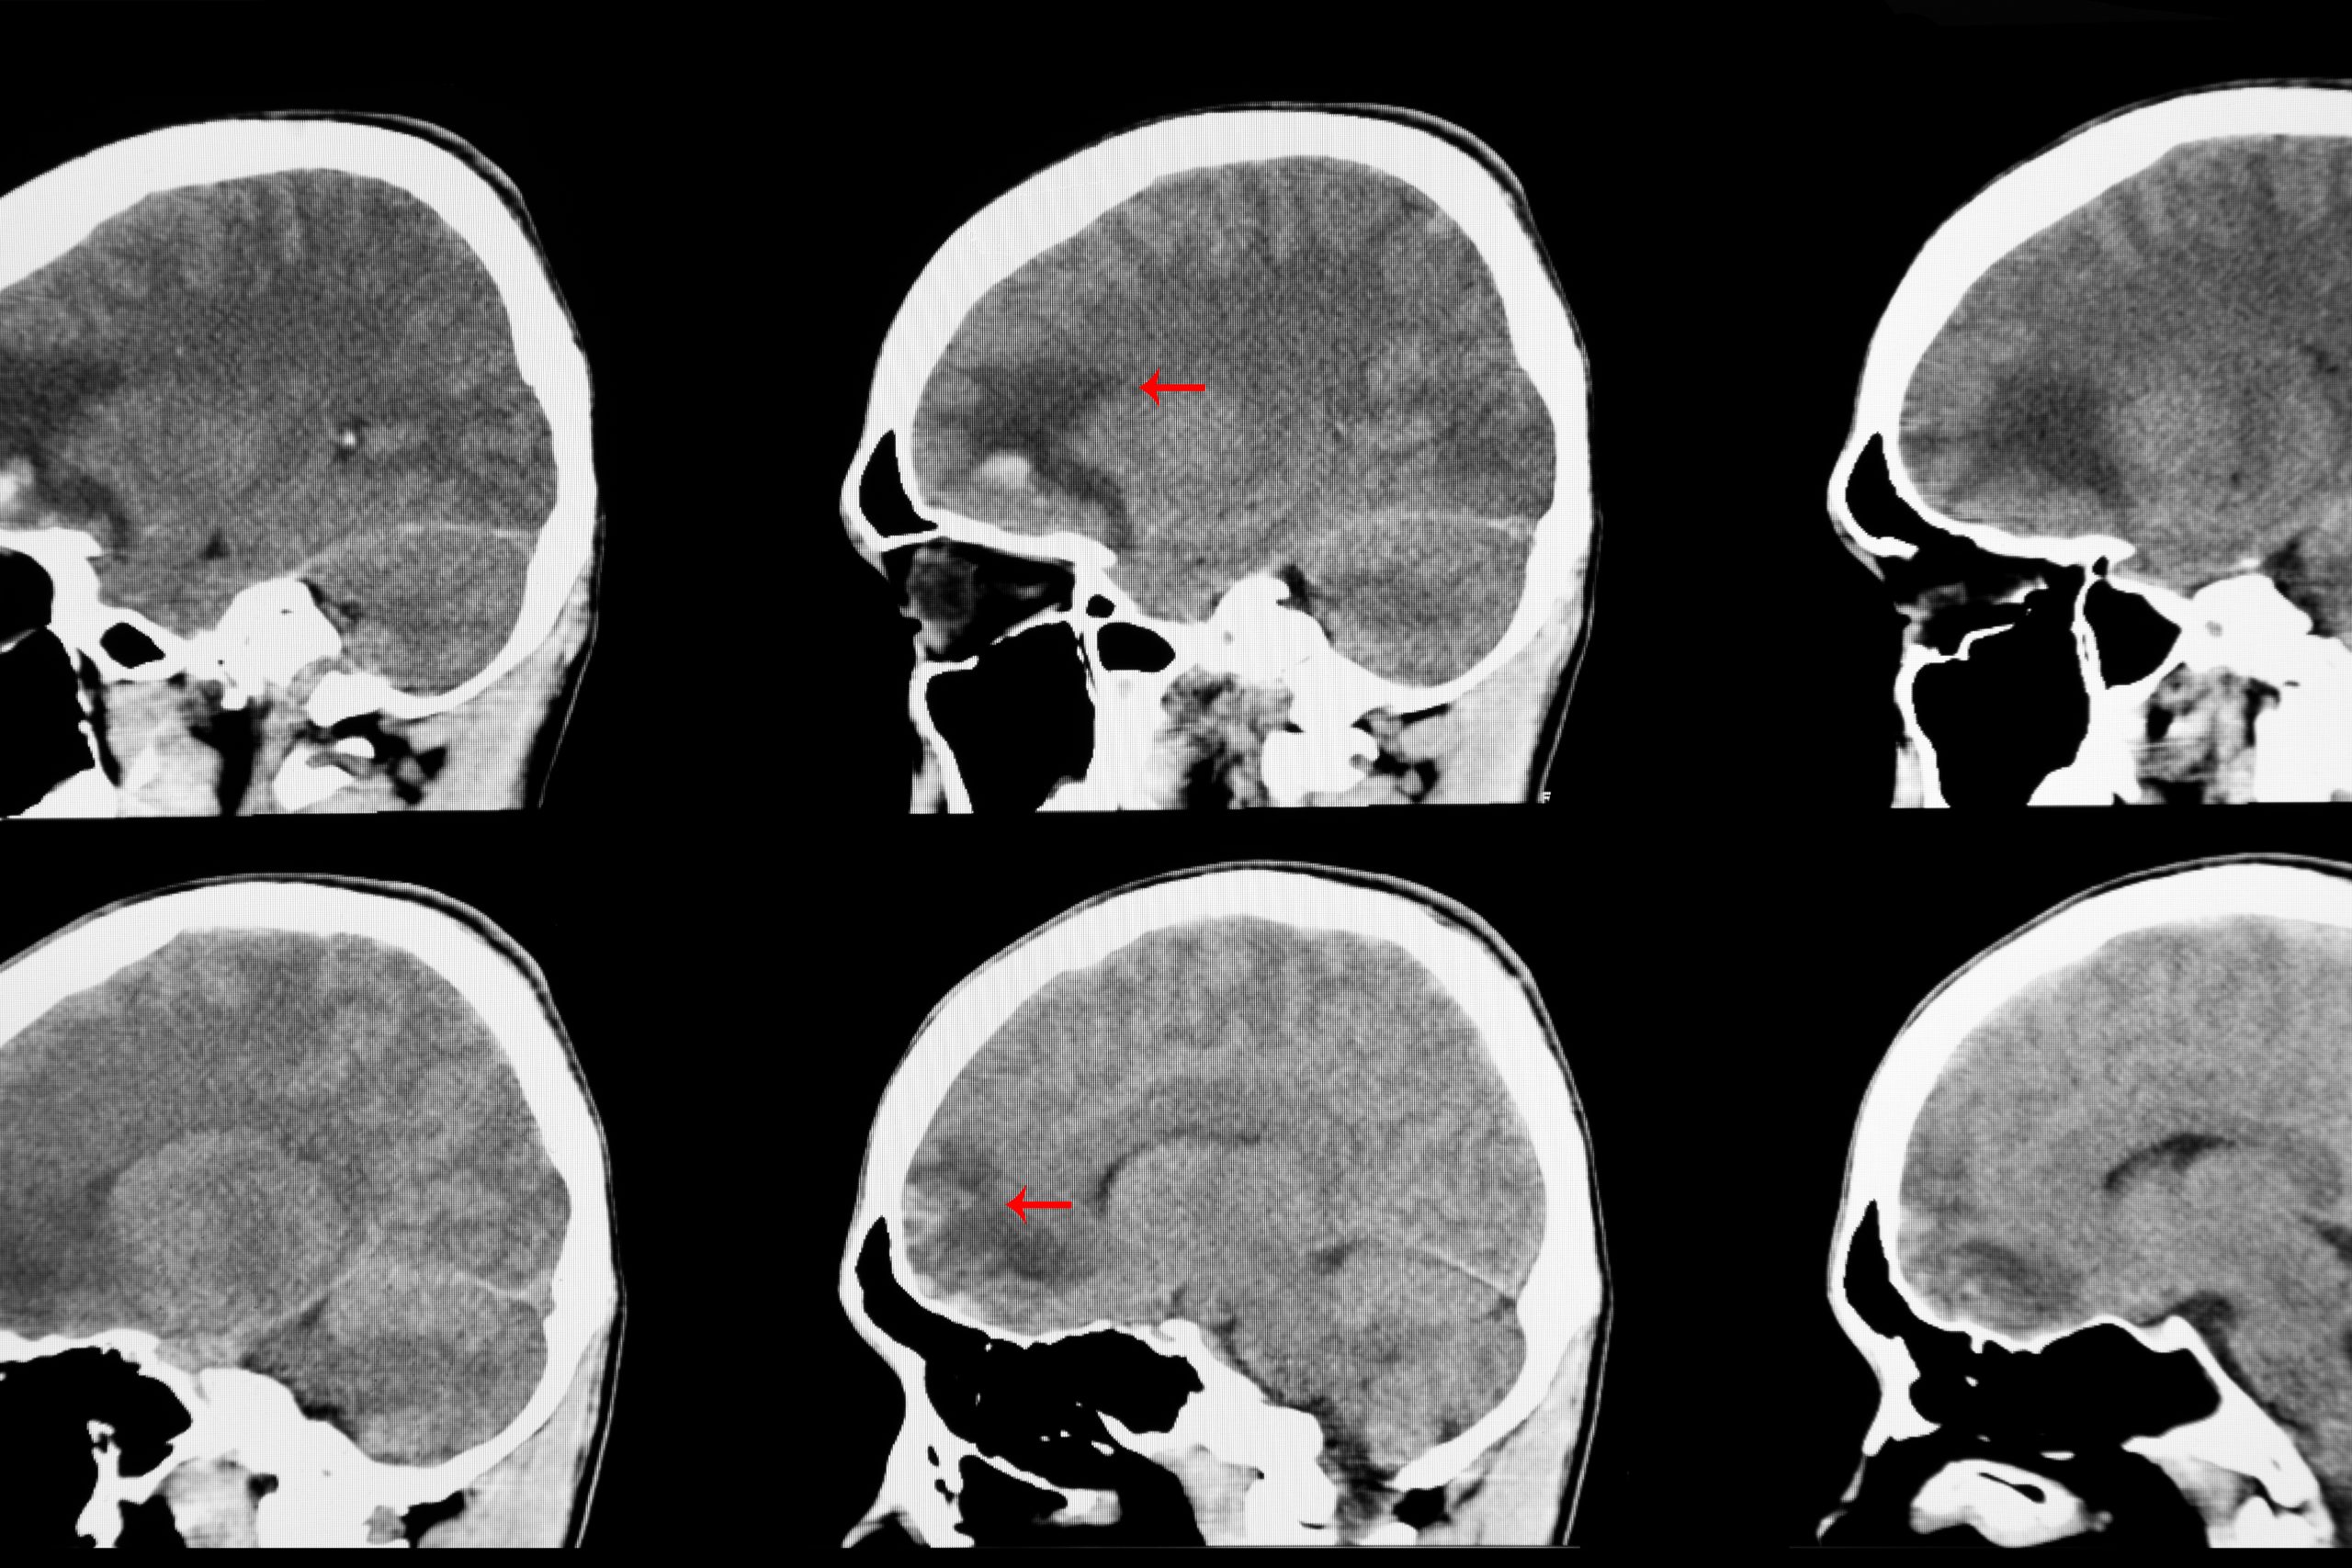

Brain tissue swelling can be dangerous. Increased intracranial pressure requires emergency surgery (craniotomy) to help alleviate the pressure in the brain. A CT of the brain is the preferred imaging used to detect and assess intracranial hematomas (bleeding) and contusions. If the finding of the CT is good, with no significant signs of injury, then no surgical management is pursued. However, close observation, repeat imaging every six hours until images are stable, anti seizure medication administration, constant blood pressure monitoring, and neurological exams every 2 hours are necessary. Patients must be monitored closely to prevent hypotension (low blood pressure), hypertension (high blood pressure), hyponatremia (low sodium), and hypercapnia (increased CO2 levels in the blood caused by abnormal respirations). A change in mentation is a cause for repeated imaging. No one patient recovers from a cerebral contusion in the same way. Recovery depends on the initial Glasgow Coma Scale (GCS), the size and location of the contusion, the age of the patient, CT Brain results, and surgical versus non-surgical treatment.

Tomatheart. (2019). CT brain scan image of a recent traumatic brain injury patient showing braincontusion and hemorrhage at frontal load with subarachnoid bleeding at the base of skull. [CT brainimage]. https://www.shutterstock.com/image-photo/ct-brian-scan-image-recent-traumatic-1409233616